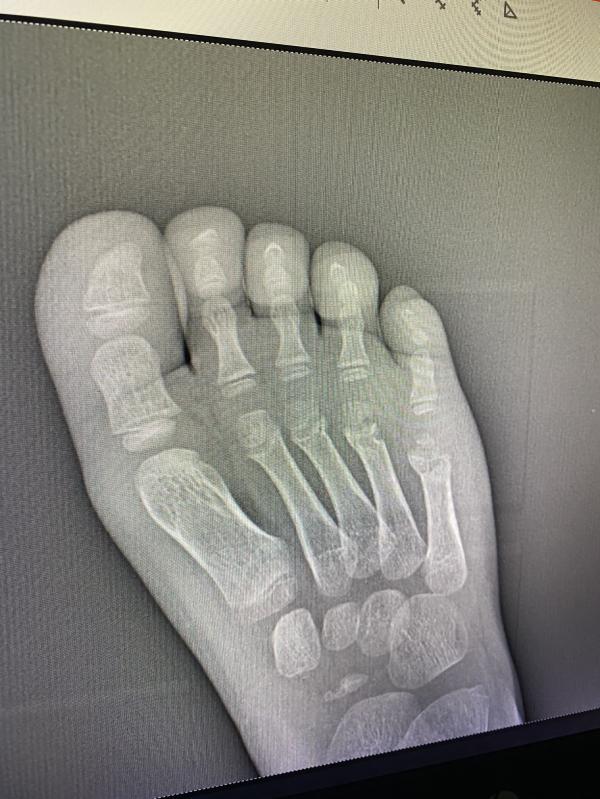

Перелом летом в гипсе: что делать? Совет ортопеда!

post image 1

Добрый день! Есть тут ортопеды? Поставили перелом, я естественно ничего не вижу🙈 и не могу принять эту ситуацию, впереди лето, а нам месяц гипса 😰

Мизинец ?

Под ним